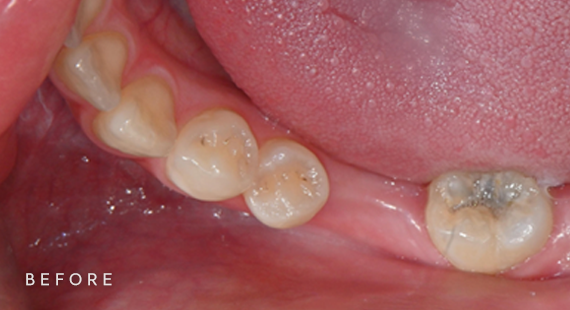

충치치료